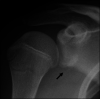

Glenoid articular cartilage lesion is a rare complication following traumatic anterior dislocation of the shoulder. We report the case of a 14-year-old male rugby player with traumatic anterior shoulder instability, an extensively flapped lesion on the glenoid articular cartilage, and an osseous Bankart lesion. Arthroscopic findings revealed that the glenoid cartilage was flap-detached, extending from the anteroinferior to the center. Repair of the osseous Bankart lesion using suture anchors and resection of the unstable peripheral part of the cartilage was performed arthroscopically. The main region of the injured articular surface was left untouched. During postoperative follow-up, absorption of the glenoid articular surface near the suture anchor holes was identified. Arthroscopic examination three months post-surgery showed that the flap detached lesion of the residual cartilage was stable and appeared adapted on the glenoid surface. The resected area was covered by fibrous tissue. A follow-up computed tomography scan revealed that the osseous lesion was united. The patient returned to his previous sports capacity eight months following the operation. At the 2-year-follow-up, magnetic resonance imaging revealed that the glenoid surface was remodeled to a flattened round shape with no signs of osteoarthritis, exhibiting proper conformity of the joint surfaces to the humeral head. Arthroscopic Bankart repair using suture anchors may cause bone resorption at the glenoid surface, leading to remodeling of the glenoid surface from the damaged glenoid cartilage lesion in young patients.